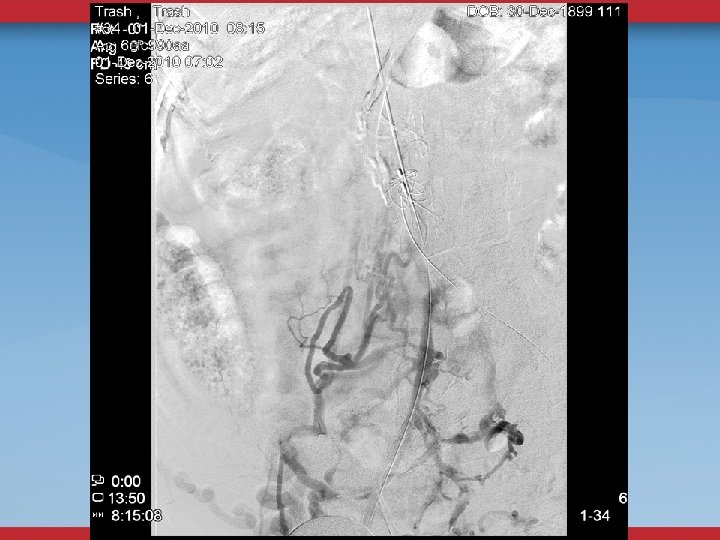

DEFINITIVE DIAGNOSTIC/THERAPEUTIC PROCEDURES VENOGRAMS UG sheath placement Femoral, Pop, PTV Flow, Collaterals

VENOGRAMS FEMORAL INFLOW FILLING DEFECTS WILL MISS SOME STENOSES, WEBS

INTRAVASCULAR ULTRASOUND THE ANATOMIC GOLD STANDARD USUALLY BILATERAL IFV/IVC CHOOSE DIAMETER/LENGTH OF BALLOON/STENT POST-STENTING ASSESSMENT